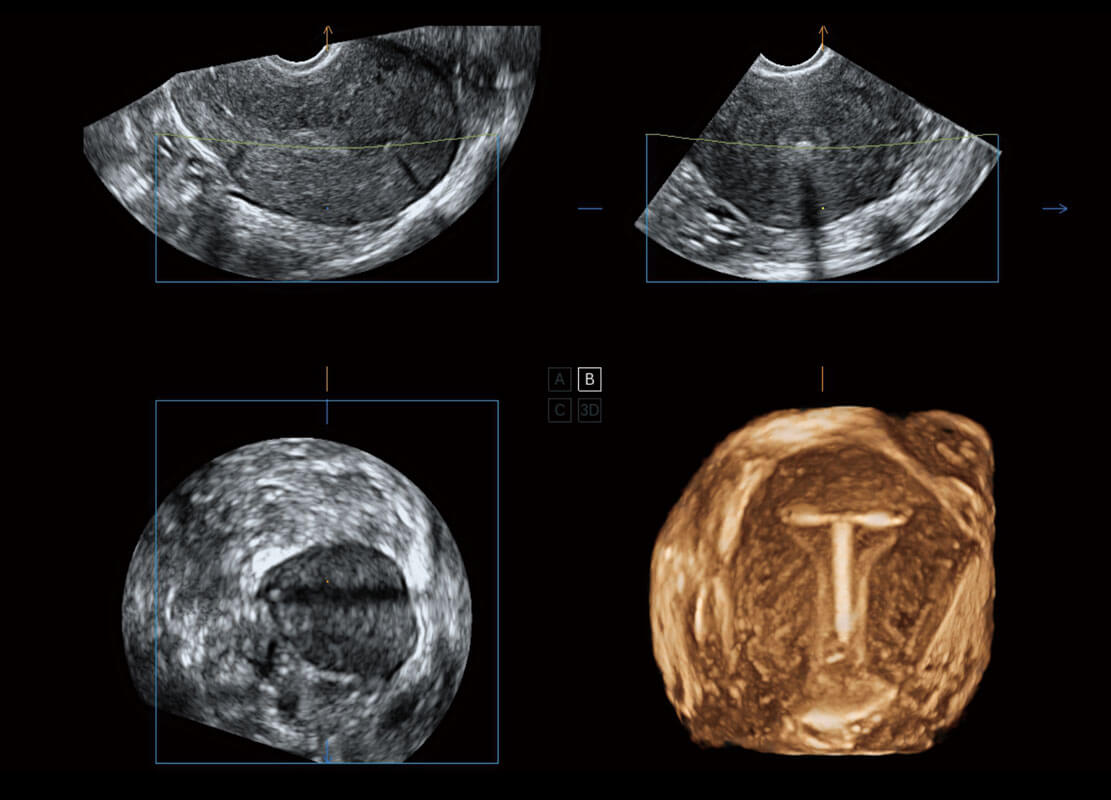

腔内三维-宫内节育器

P60搭载一系列胎儿心脏成像技术,实现精细的胎儿心脏评估。

四腔切面

四腔心血流

右室双出口

胎心容积成像